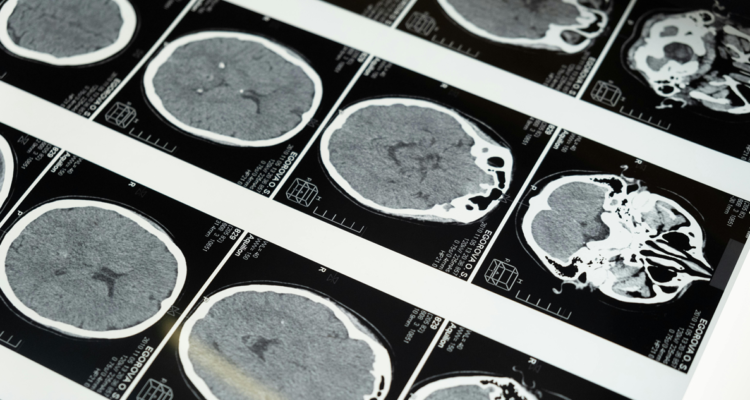

Un simple escáner cerebral podría llegar a ser la clave para encontrar el tratamiento más eficaz para la depresión.

Investigadores de Stanford Medicine lograron identificar seis sub tipos biológicos, o “biotipos”, de depresión y ansiedad, cada uno con patrones distintos de actividad cerebral, que responden de manera diferente a los tratamientos.

Este descubrimiento se basó en un análisis detallado utilizando imágenes por resonancia magnética funcional (IRMf) y aprendizaje automático.

El estudio examinó la actividad cerebral de 801 participantes con diagnósticos de trastornos como la depresión mayor y la ansiedad. Los investigadores escanearon los cerebros de los participantes tanto en reposo como mientras realizaban tareas cognitivas y emocionales, enfocándose en seis circuitos cerebrales conocidos por su implicación en la depresión.